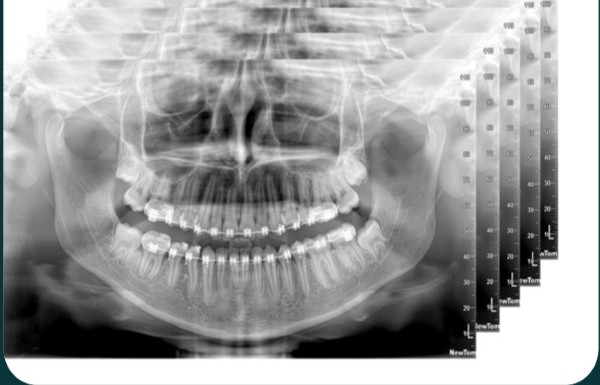

Chụp phim Panorama toàn cảnh

Chụp phim toàn cảnh (phim Panoramic) được sử dụng để quét toàn bộ cấu trúc răng, hàm và các cấu trúc lân cận như xoang, hàm mặt. Loại hình này thường được chỉ định trong các ca phẫu thuật, trồng răng, phát hiện các vấn đề về xương hoặc các bất thường bên trong khung hàm.

Chỉ với khoản chi phí khoảng 300.000 – 700.000 đồng, bạn đã có thể sở hữu một hình ảnh toàn diện, giúp bác sĩ có hướng xử lý phù hợp nhất. Công nghệ hiện đại của máy phim toàn cảnh giúp giảm thiểu phóng đại, hạn chế nhiễu và nâng cao độ chính xác của kết quả. Đây là lựa chọn tối ưu để có cái nhìn tổng thể, đặc biệt phù hợp cho các ca điều trị phức tạp.